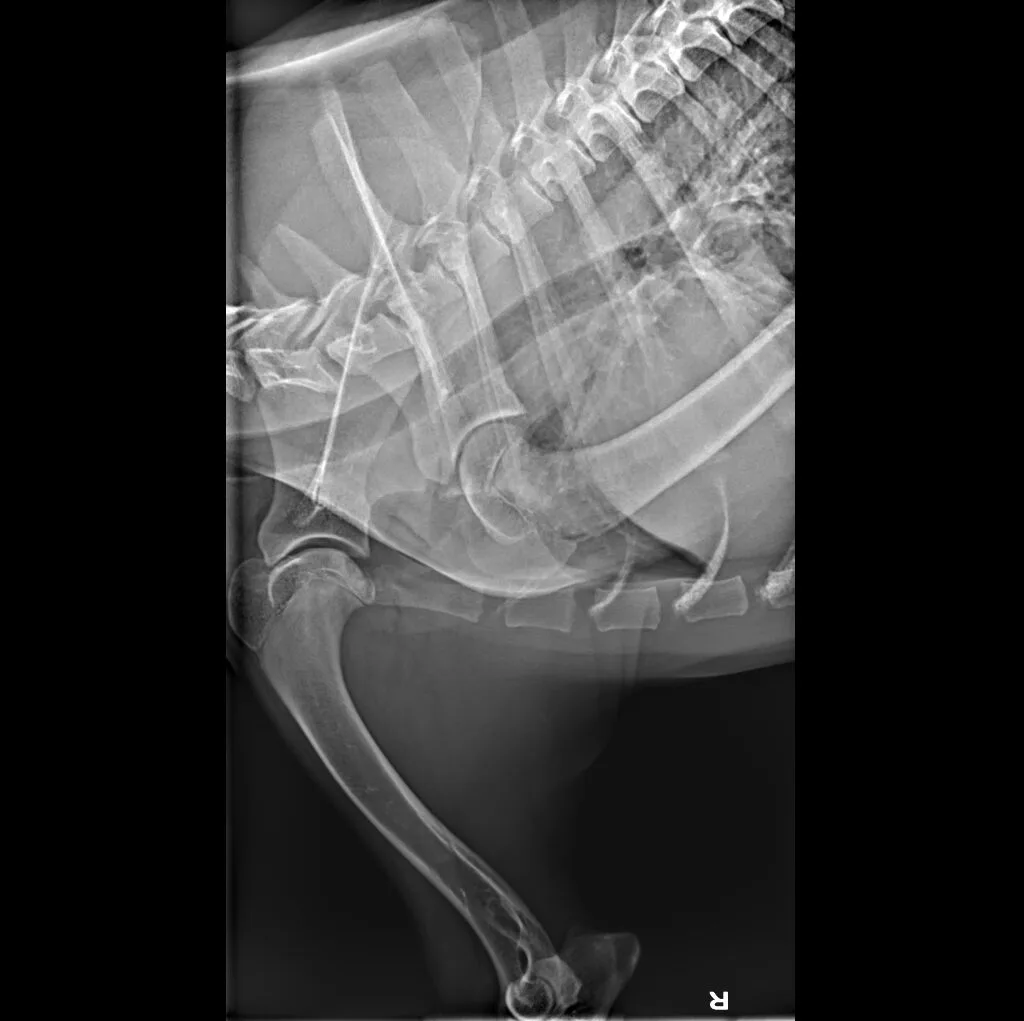

At Grand Ave. Pet Hospital, we utilize digital radiography to diagnose and monitor a wide range of medical conditions in pets. Digital X-rays provide clearer images, faster results, and safer radiation levels, ensuring the best possible care for your furry companion.

Digital radiography offers superior imaging quality and precision compared to traditional X-ray techniques. It allows us to detect hidden health issues early, leading to faster and more effective treatments.

🔹 Abdominal & Gastrointestinal Issues – Detecting obstructions, tumors, or organ abnormalities